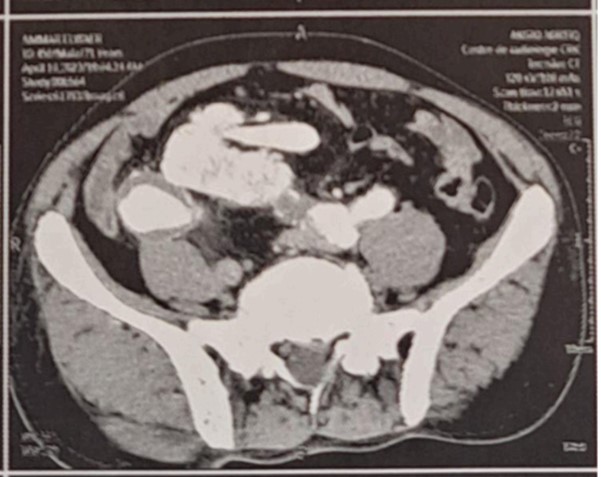

A 73-year-old man with a history of nephrolithiasis presented with abdominal pain. Computed tomography angiography (CTA) demonstrated an 89 mm infrarenal AAA extending to the iliac arteries, with the left iliac artery measuring 32 mm and the right iliac artery 27 mm. An ectopic right pelvic kidney was identified, perfused by the right internal iliac artery. Baseline renal function was preserved, with creatinine clearance at 54.7 ml/min/1.73m².

Figure: Computed tomography angiography (CTA) demonstrated an 89 mm infrarenal AAA extending to the iliac arteries, with the left iliac artery measuring 32 mm and the right iliac artery 27 mm. An ectopic right pelvic kidney was identified, perfused by the right internal iliac artery.